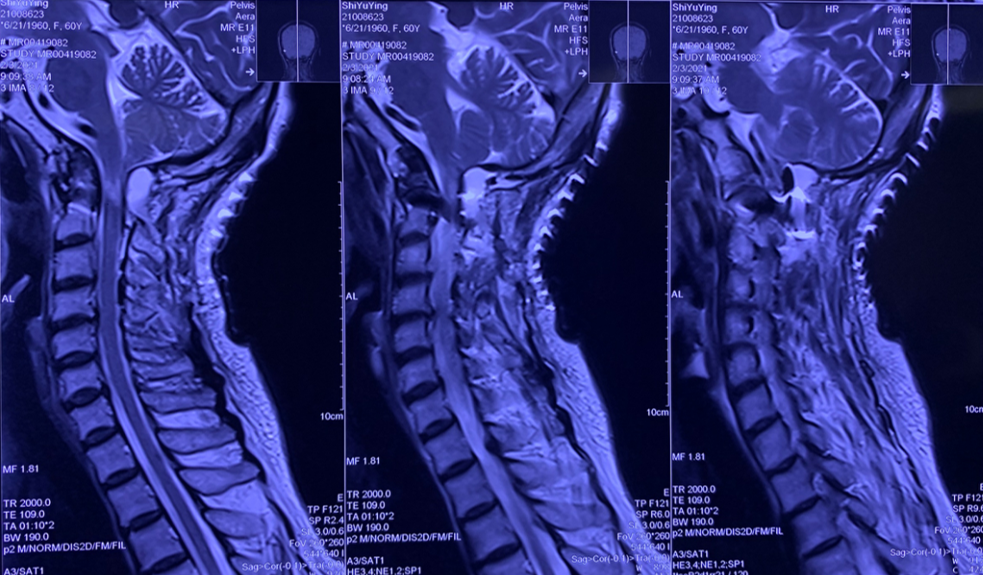

颈髓MRI:

颅底凹陷症、寰枕融合;寰枢关节脱位并延髓脊髓变性或损伤;颈椎退行性变;C2/3、C3/4、C4/5、C5/6、C6/7椎间盘突出并C4/5水平椎管狭窄。

患者术前部分影像学资料

影像学资料显示寰枢椎脱位,脊髓受压明显